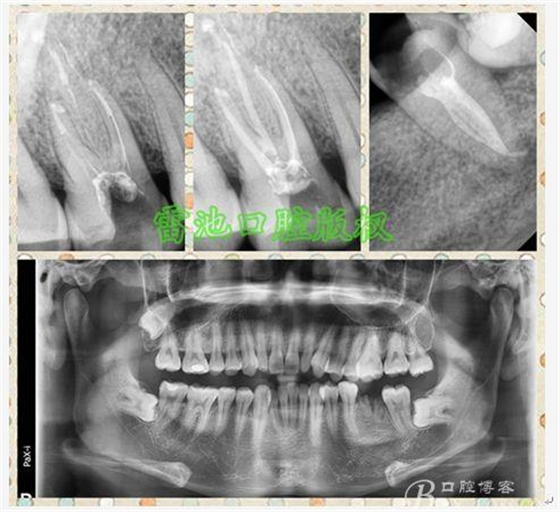

E、X線影像學的檢查研判能力:這點不需要強調(diào)太多,對于普通的非CBCT的二維影像對醫(yī)生讀片能力有一定的要求,有個逐步提高的過程,非一蹴而就,需要學會把二維的X線影像與三維的解剖結(jié)構(gòu)進行良好的對應結(jié)合,對于某些鈣化的髓室底,應通過想象把根管口的分布、根管的走向以及各種變化通過想象投射到對應的髓室底上;

1、查閱各種文獻,MB2的發(fā)生率在52-96%之間,治療時遺漏是上頜磨牙根管治療失敗的主因,2、一般位于MB1根管口與腭根管口方向的0.5-5mm范圍內(nèi),而大多數(shù)都位于MB舌側(cè)的1-3mm處,其中2mm以內(nèi)占85.7%,3、MB1-P根管口連線與MB1-MB2根管口的連線夾角大部分(74.3%)在30度以內(nèi);4、MB2的尋找大部分需要去除相應部位的牙本質(zhì);5、當找到的MB根管口呈“長線型”且有深色凹線向舌側(cè),或者找到的MB根管口明顯偏頰多提示有MB2的可能;6、DOM(牙科手術(shù)顯微鏡)的使用有助于找尋MB2;

H、關于下磨牙MM根管的重視問題: